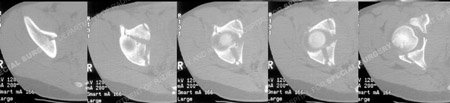

CT scans images further delineate the fracture pattern.